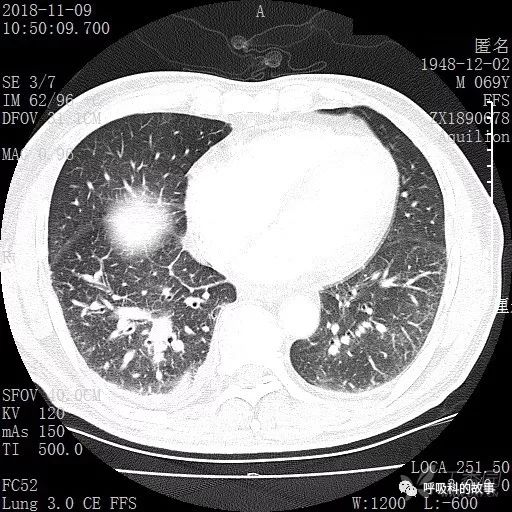

胸部增强CT示右肺门占位伴远端阻塞性肺炎,纵膈、右肺门、右侧颈根部、右侧腋下及肝门部肿大淋巴结。两侧胸腔少量积液。

肺窗CT